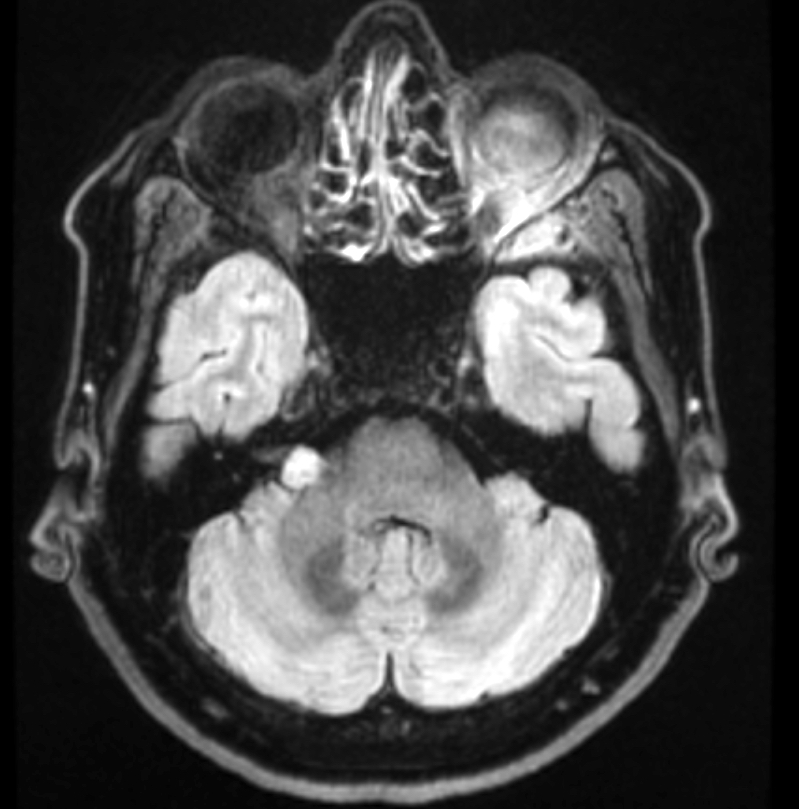

Radiology description

- Well circumscribed masses that displace adjacent structures without direct invasion

- On MRI, it may be

- Iso or hyperintense in T2 weighted images (Spine (Phila Pa 1976) 2017;42:E150)

- Hyperintense in fluid attenuated inversion recovery (FLAIR) images

- Heterogeneous or homogeneous enhancement in T1 weighted sequences (J Clin Imaging Sci 2017;7:38)

Radiology images